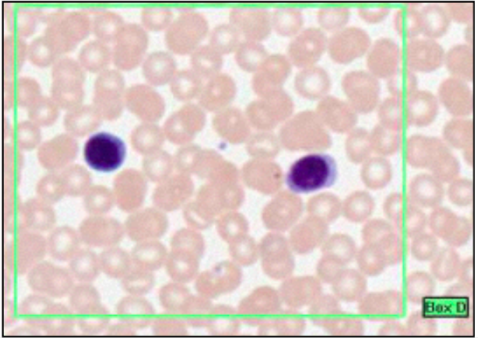

MONOCYTES

- kidney-shaped nucleus

- no granules

- pale blue cytoplasm

- immature cells which differentiate to one of various forms when leave blood and enter connective tissue

- many to macrophages (fixed marcophage @ liver = Kupffer, and @ spleen)

in blood and alveolar air spaces

macrophage phagocytotic, actute inflammation, arrive after neutrophils